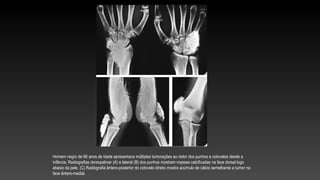

Homem negro de 66 anos de idade apresentava múltiplas tumorações ao redor dos punhos e cotovelos desde a

infância. Radiografias dorsopalmar (A) e lateral (B) dos punhos mostram massas calcificadas na face dorsal logo

abaixo da pele. (C) Radiografia ântero-posterior do cotovelo direito mostra acúmulo de cálcio semelhante a tumor na

face ântero-medial.